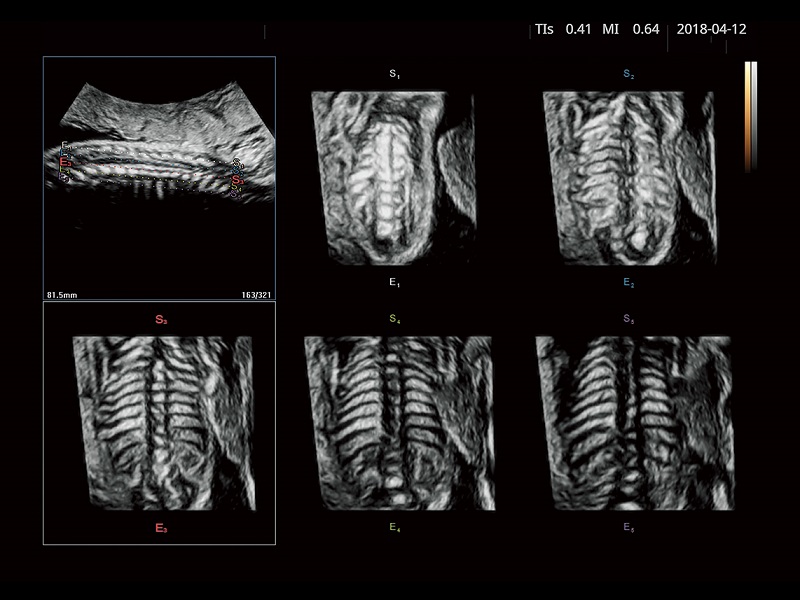

FUTUS features great imaging technologies to support a clear view and confident diagnoses.